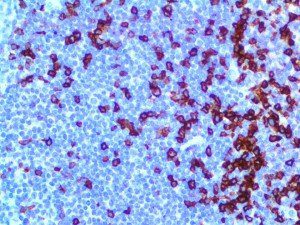

It is the ICU physician who is most likely to witness one of the deadliest manifestations of the abnormal immunological response, the cytokine storm syndrome (CSS). This response is also referred to by some as the cytokine release syndrome (CRS). CSS is characterized by continuous activation and expansion of macrophage and lymphocyte populations, which secrete large amounts of cytokines, causing the cytokine storm. This massive cytokine release is akin to hemophagocytic lymphohistiocytosis (HLH) disease, a syndrome characterized by initial unchecked and persistent activation of cytotoxic T lymphocytes and NK cells.

Clinical and laboratory manifestations of HLH include fever, enlarged liver and/or spleen, neurologic dysfunction, coagulopathy, liver dysfunction, cytopenias (i.e., low levels of erythrocytes, leukocytes, and/or platelets), hypertriglyceridemia, hyperferritinemia, hemophagocytosis, and eventually diminished NK cell activity as the immune system becomes progressively paralyzed. HLH can be familial (primary HLH) or secondary to another disease process (sHLH), such as rheumatic disease, in which it is referred to as macrophage activation syndrome (MAS, characterized by elevated ferritin).